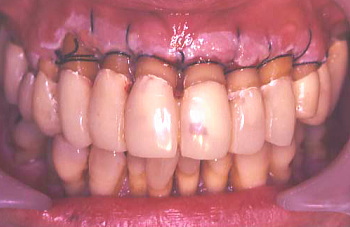

③ 上の前歯は少しぐらぐらするので、歯と歯の間をボンドで止め固定した。患者の熱心な歯磨きにより前回よりいっそう歯肉が引き締まり健康になった。しかし歯周ポケットは深いままなので外科によりポケットを除去しなければならない。この状態は治ったように見えるが、これは見せかけの治癒で本当は完治していない。

④ 外科処置前に上の歯の虫歯治療と6本の歯の動揺(ぐらぐら動くこと)防止目的で歯を削り6本をひとまとめにした仮り歯を入れ、固定しなければならない。

⑤ 上の歯に仮り歯を装着した状態。このあと歯周ポケット除去を行う外科手術に移る。